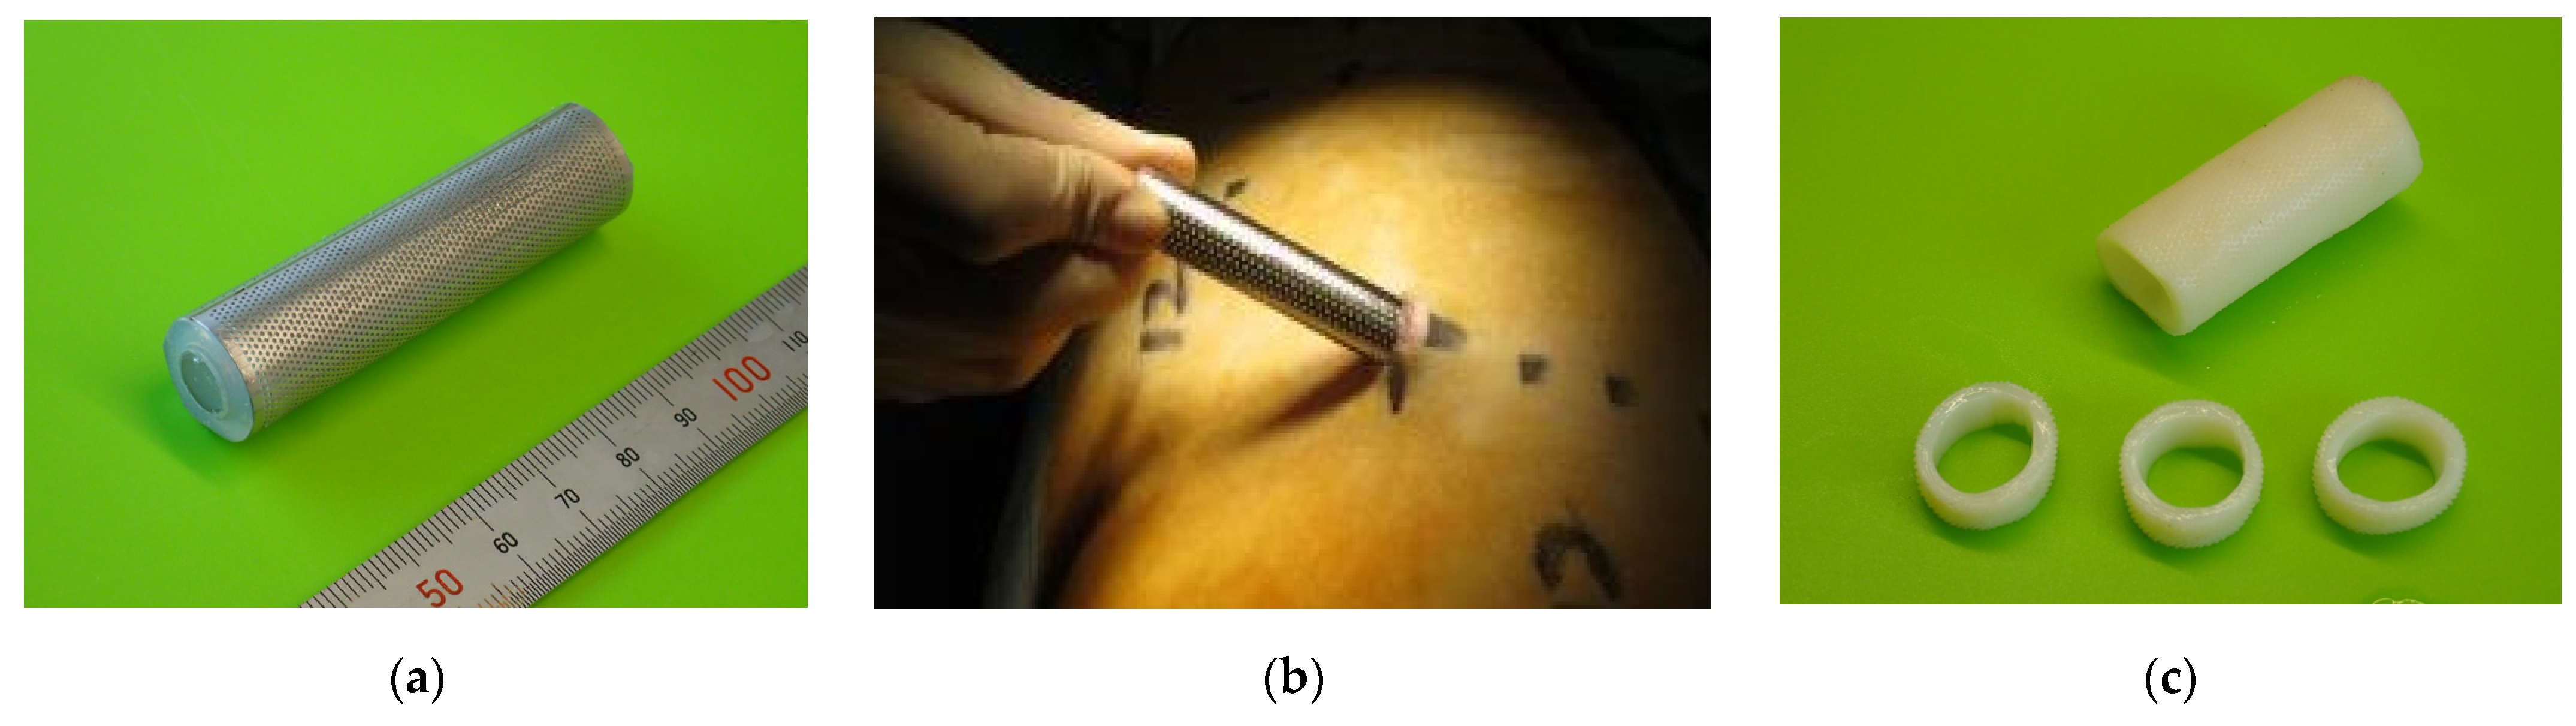

2.1. Biotube Production